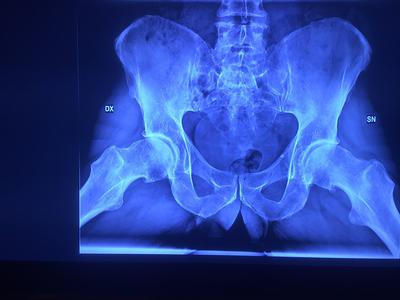

The doctor says I could be looking at an operation in 2 to 3 years (see images), which I found rather alarming.

You do indeed have early hip arthritis on both sides, and I doubt if any of the three alternatives appeal to you. But I can assure you, there is life after marathon running. It's just time to find another sport.